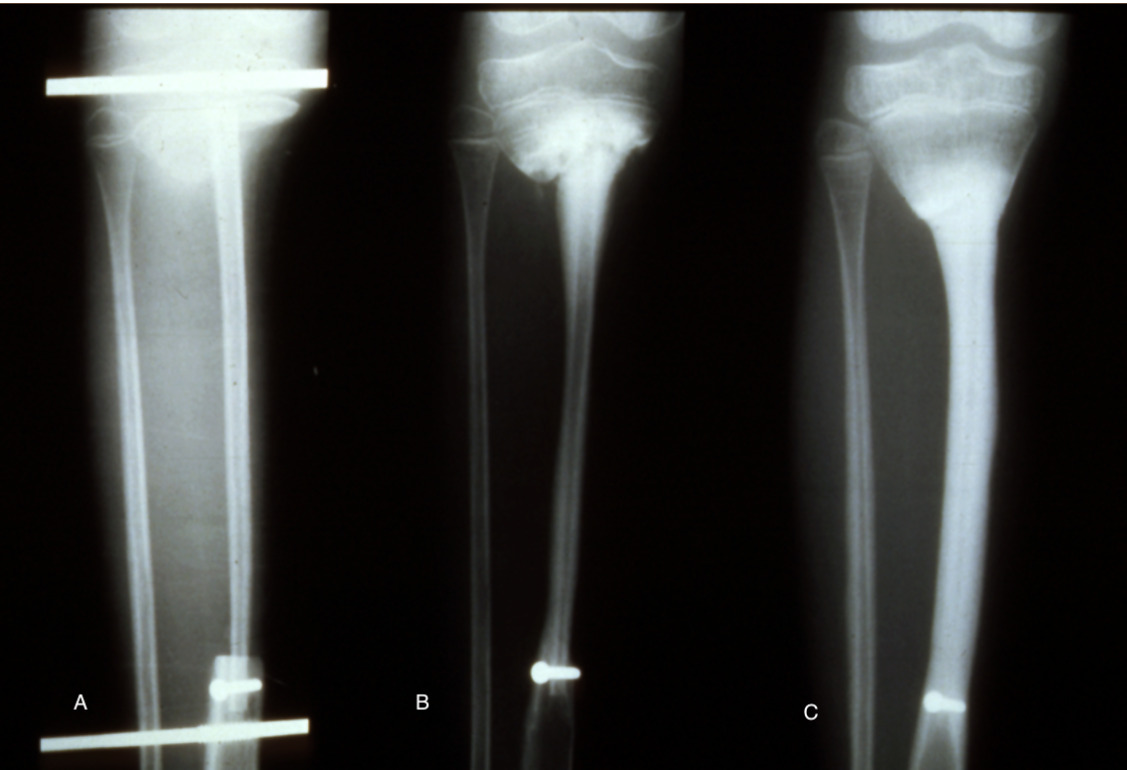

Another form of fixation is an intramedullary nail or rod used in two of our nine cases of resection of a pseudarthrosis of the tibia in a child shown in Cases 12 and 13 (Figures 32 and 33). In these two cases, the distal tibial fragment could not be fixed to the fibula with a screw. Instead a Rush nail was passed from below through the heel, calcaneum, talus and distal tibia and into the medullary cavity of the transplanted fibula. The result was exactly the same as the other seven cases. Even in plaster you can’t keep a child still! By six weeks all, including the two with nails, showed union and early bone hypertrophy (Figures 32 and 33).

The importance of centralising the fibula within the medullary cavity of the femur or tibia is again reinforced by another case done at the Royal Melbourne Hospital. The fibula was used to reconstruct the femur but fixed rigidly with a plate and screws in Case 14 (Figure 34A). Twelve months later there was union but no sign of hypertrophy of the transplant. Then the plate broke. A Kuntscher nail was inserted from above and down through the medullary cavity of the fibula. It shattered forming a row of ‘bangles’ around the nail (Figure 34B). Two years later, having walked on his ‘box of bones skewered by the K-nail,’ he was located and the leg radiographed. Except for one level, there was union and hypertrophy of all bone bangles (Figure 34C).